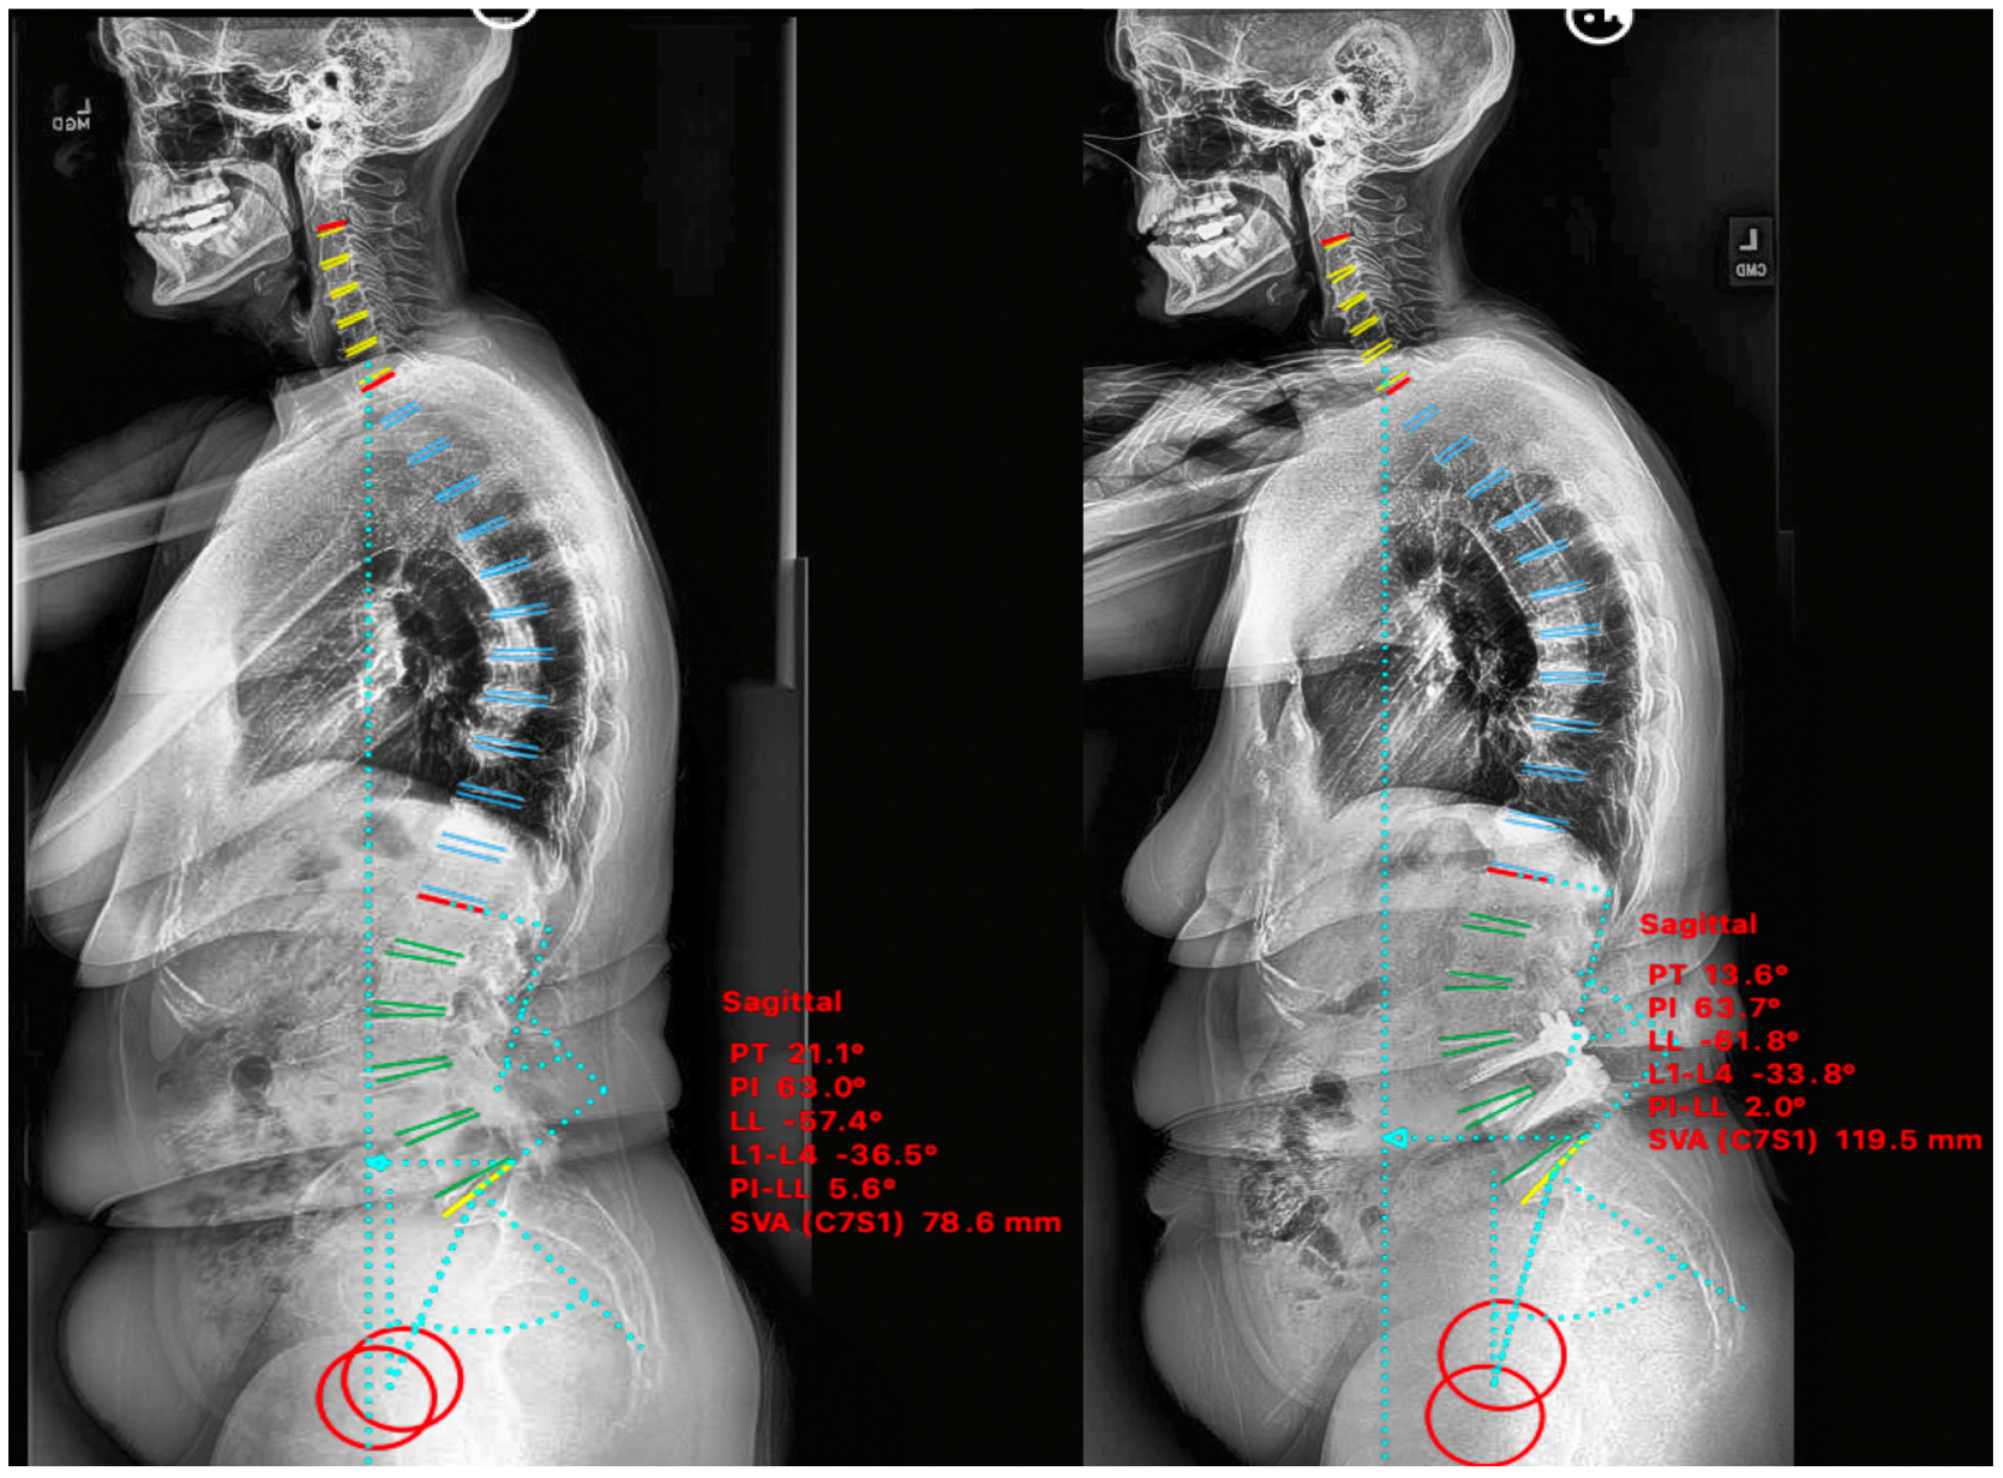

2.4.1. Case I

2.4.2. Case II